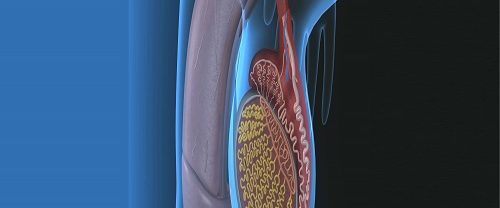

Total Kalça Protezi Replasmanı Nedir? Total Kalça Protezi Replasmanı, yaygın olarak kalça eklemi sorunları yaşayan ve bu sorunlar nedeniyle yaşam kalitesi önemli ölçüde düşen kişilere uygulanan bir cerrahi işlemdir. Bu işlem, kalça eklemi üzerindeki ağrıyı, kısıtlamayı ve fonksiyonel bozuklukları hafifletmek veya ortadan kaldırmak için gerçekleştirilir. Genellikle kalça eklemi dejeneratif hastalıklar (örneğin osteoartrit) veya kalça kırıkları…

Total Kalça Artroplastisi Nedir? Total kalça artroplastisi, kalça ekleminin kronik ağrı, kısıtlı hareketlilik ve diğer sorunlara neden olan hastalıklı veya yıpranmış kısımlarını değiştirmek için cerrahi bir prosedürdür. Bu işlem, kalça ekleminin doğal yapılarını yerine titanyum, seramik veya plastik gibi dayanıklı ve biyolojik olarak uyumlu malzemelerden yapılmış protezlerle değiştirir. Detaylar: Kalça Eklemi Sorunları: Total Kalça Artroplastisi…